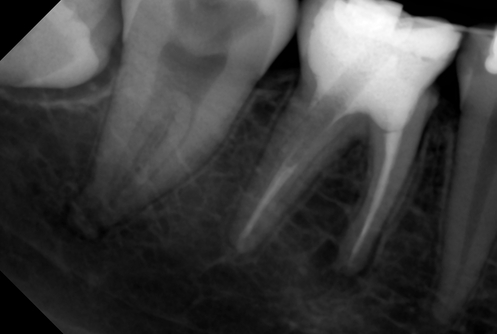

В стоматологической клинике "5 Принципов" в Симферополе мы гордимся тем, что каждый пациент получает индивидуальный подход и безупречный результат в области эндодонтического лечения под микроскопом. Наши специалисты применяют современные цифровые технологии, микропроцессорные и нейромодуляционные инструменты, что позволяет достичь максимальной точности и минимального дискомфорта. В портфолио клиники — широкий спектр кейсов: от первичной диагностики пульпита до сложной ретенированной резорбции и повторной эндодонтии. Мы беремся за зубы любых степеней сложности: от моляра до резцов, используя щадящие концевые инструменты и безболезненные методы постоянной анестезии. Все процедуры проходят под увеличением, что обеспечивает точное удаление инфицированной ткани и сохранение естественной анатомии зуба.Особое внимание мы уделяем постпроцедурному наблюдению: контроль за герметичностью заполнения корневых каналов, профилактические рекомендации и возможная корректировка плана лечения при необходимости. В "5 Принципах" мы разумно сочетаем комфорт, эстетическую привлекательность и долгосрочную функциональность. Результат — здоровые зубы, уверенная улыбка и спокойствие наших пациентов в Симферополе. Запишитесь на консультацию и убедитесь сами в нашем подходе к качественному эндодонтическому лечению.